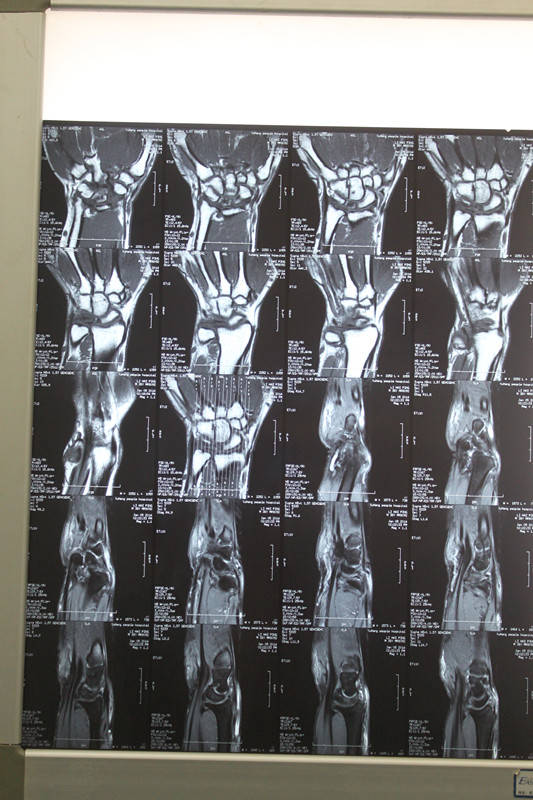

[手部疾病] 月骨缺血性坏死

患者  36岁  无外伤性腕关节疼痛,